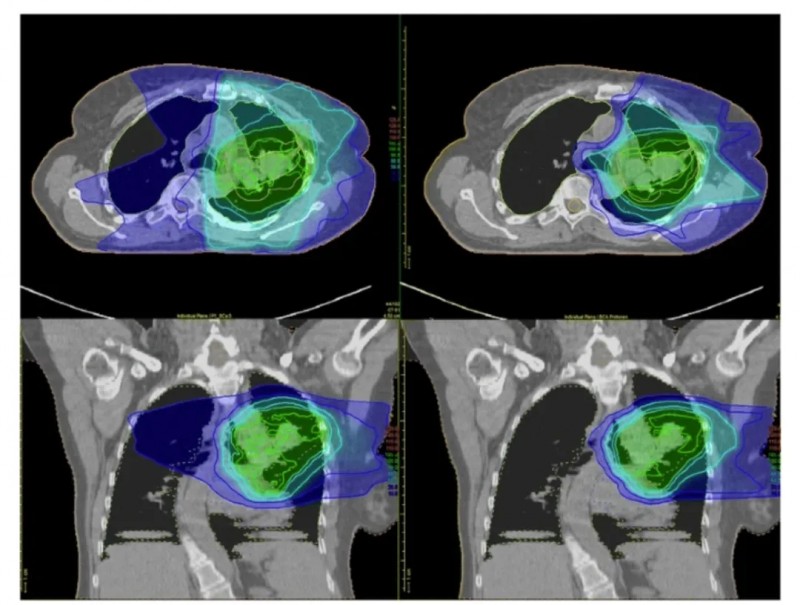

值得一提的是,在靶区剂量分布和器官受累剂量上,质子组同样展现优势:与X线组相比,质子组的肿瘤临床靶区(CTV)和射野更小,且肺部剂量(V5、V20、平均肺剂量MLD)、心脏剂量(V40、最大剂量Dmax)均更低,上述差异均具有统计学意义(P <0.05)。下图A为X射线调强放射治疗(IMRT)的剂量分布,图B为固定角度质子治疗的剂量分布。

▲图源“SPRINGER LINK”,版权归原作者所有,如无意中侵犯了知识产权,请联系我们删除

质子治疗能有效规避此类风险。下图以局部晚期非小细胞肺癌(NSCLC)患者为例,对比了调强放射治疗(IMRT,左图)与质子治疗(右图)的辐射剂量分布:传统放疗会将辐射传递至肿瘤及周围大片健康组织,而质子治疗可将绝大部分辐射集中于肿瘤区域,对危及器官(OAR)的辐射剂量显著更低。

▲图源“BMC”,版权归原作者所有,如无意中侵犯了知识产权,请联系我们删除